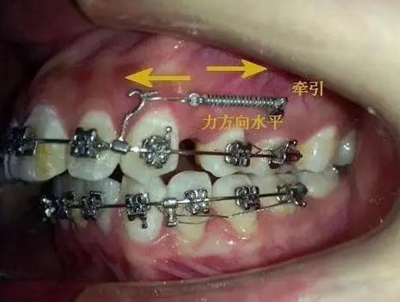

考慮到如果能像種植支抗,水平方向或者向唇側(cè)牽引移動(dòng),可以有效避免垂直方向牽引力壓迫側(cè)切牙根尖部,所以我和病人溝通了一下,建議采用種植支抗,但是病人不想增加費(fèi)用。

那好吧還是采用輔弓增加支抗,經(jīng)濟(jì)適用,也便與操作,0.8不銹鋼絲彎制,進(jìn)行熱處理,增加其彈力。

考慮了一下沒有采用其他輔助裝置和種植支抗,還是采用輔弓增加支抗,經(jīng)濟(jì)適用,也便與操作,0.8不銹鋼絲彎制,進(jìn)行熱處理,增加其彈力。

結(jié)扎固定后開始牽引尖牙向遠(yuǎn)中,